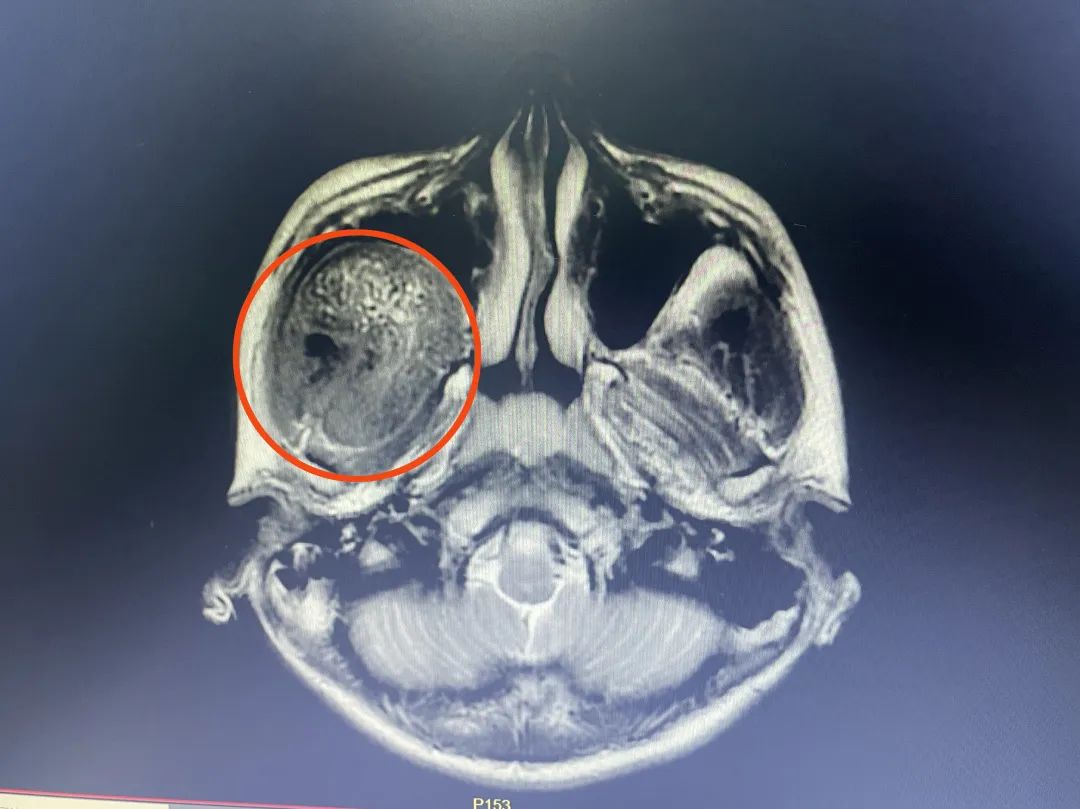

CT检查显示,患者肿瘤有鸡蛋大小